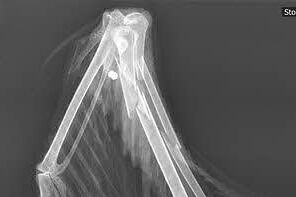

Knochenbrüche nach Kollisionen

Schussverletzungen (2017 - Luther)  Foto: Tierklinik

Kollisionen

Leitungsanflug - Kabel

• Kollisionen mit Stromleitungen z. B. im Nebel oder bei Panik, durch Unerfahrenheit.

• Enden oft mit Knochenbrüchen unterschiedlichen Grades, aber auch mit dem Tod z. B. durch innere Blutungen.

Schussverletzungen

• Die Tiere sterben häufig nicht sofort an den Schussverletzungen, sondern auch durch den Absturz aus großer Höhe.

• Manchmal werden die Kugeln im Körper durch Verkapselung isoliert, können aber später Probleme bereiten.

• Bei Bleimunition ist auch eine langsame Vergiftung (siehe dort) möglich.